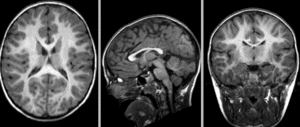

RegLib C42 unregistered.gif baseline and follow-up before registration (click to enlarge)

RegLib C42 affine.gif after affine alignment. Note the residual shape differences (click to enlarge)